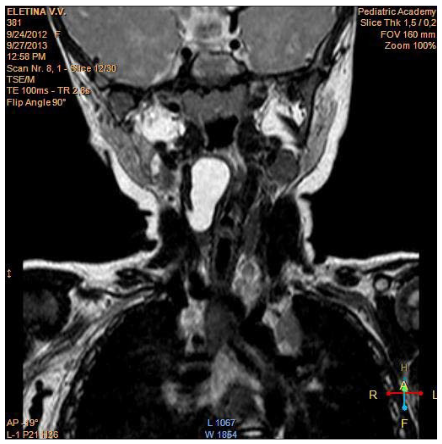

When fibro laryngoscopy revealed a rounded formation of the right vysokopalonadgortnaya fold almost completely overlapping the lumen of the larynx (Figure 1). On a series of MRI tomograms of the soft tissues of the neck from the level of C2 to the level of C5-6 in the projection of the right pear-shaped sinus is determined by a cyst with clear uneven contours, which has an irregular rounded shape. The size of the cyst is 11x16x28mm. Cyst significantly shifts the right scooped-nadgortnaya fold to the left. Its lower edge is traced at the level of the subglottic space (Figure 2-4).

Figure 4:MRI, frontal projection.